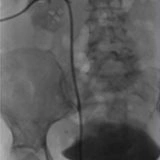

Posizionamento di Stent Nefro-Vescicale

In alcuni casi, viene posizionato uno stent nefro-vescicale quando il drenaggio esterno non è più necessario o desiderato dal paziente. Questo stent può essere posizionato anche in urgenza, ad esempio in presenza di infezioni gravi, insufficienza renale acuta o in pazienti con un solo rene. La sostituzione periodica degli stent può essere eseguita endoscopicamente dall’urologo o sotto guida radiologica dal radiologo interventista, con una procedura rapida e a basso rischio in regime di day surgery.